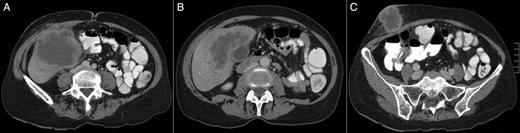

(A–C) A CT scan revealing a large hepatic mass invading the abdominal wall.

The present case was a diagnostic trap. First, the patient's skin lesion presented as a cutaneous abscess and was treated as such, and then the skin biopsy revealed a squamous cell cancer. Clinical examination and CT scan suggested a continuous mass involving the abdominal wall and liver. CM was only suspected during surgery when no continuity between the liver tumour and the abdominal wall was identified. It is interestingly to note that recurrence first occurred at skin and adrenals, which can be probably explained by the ectodermal origin of the medullary area.